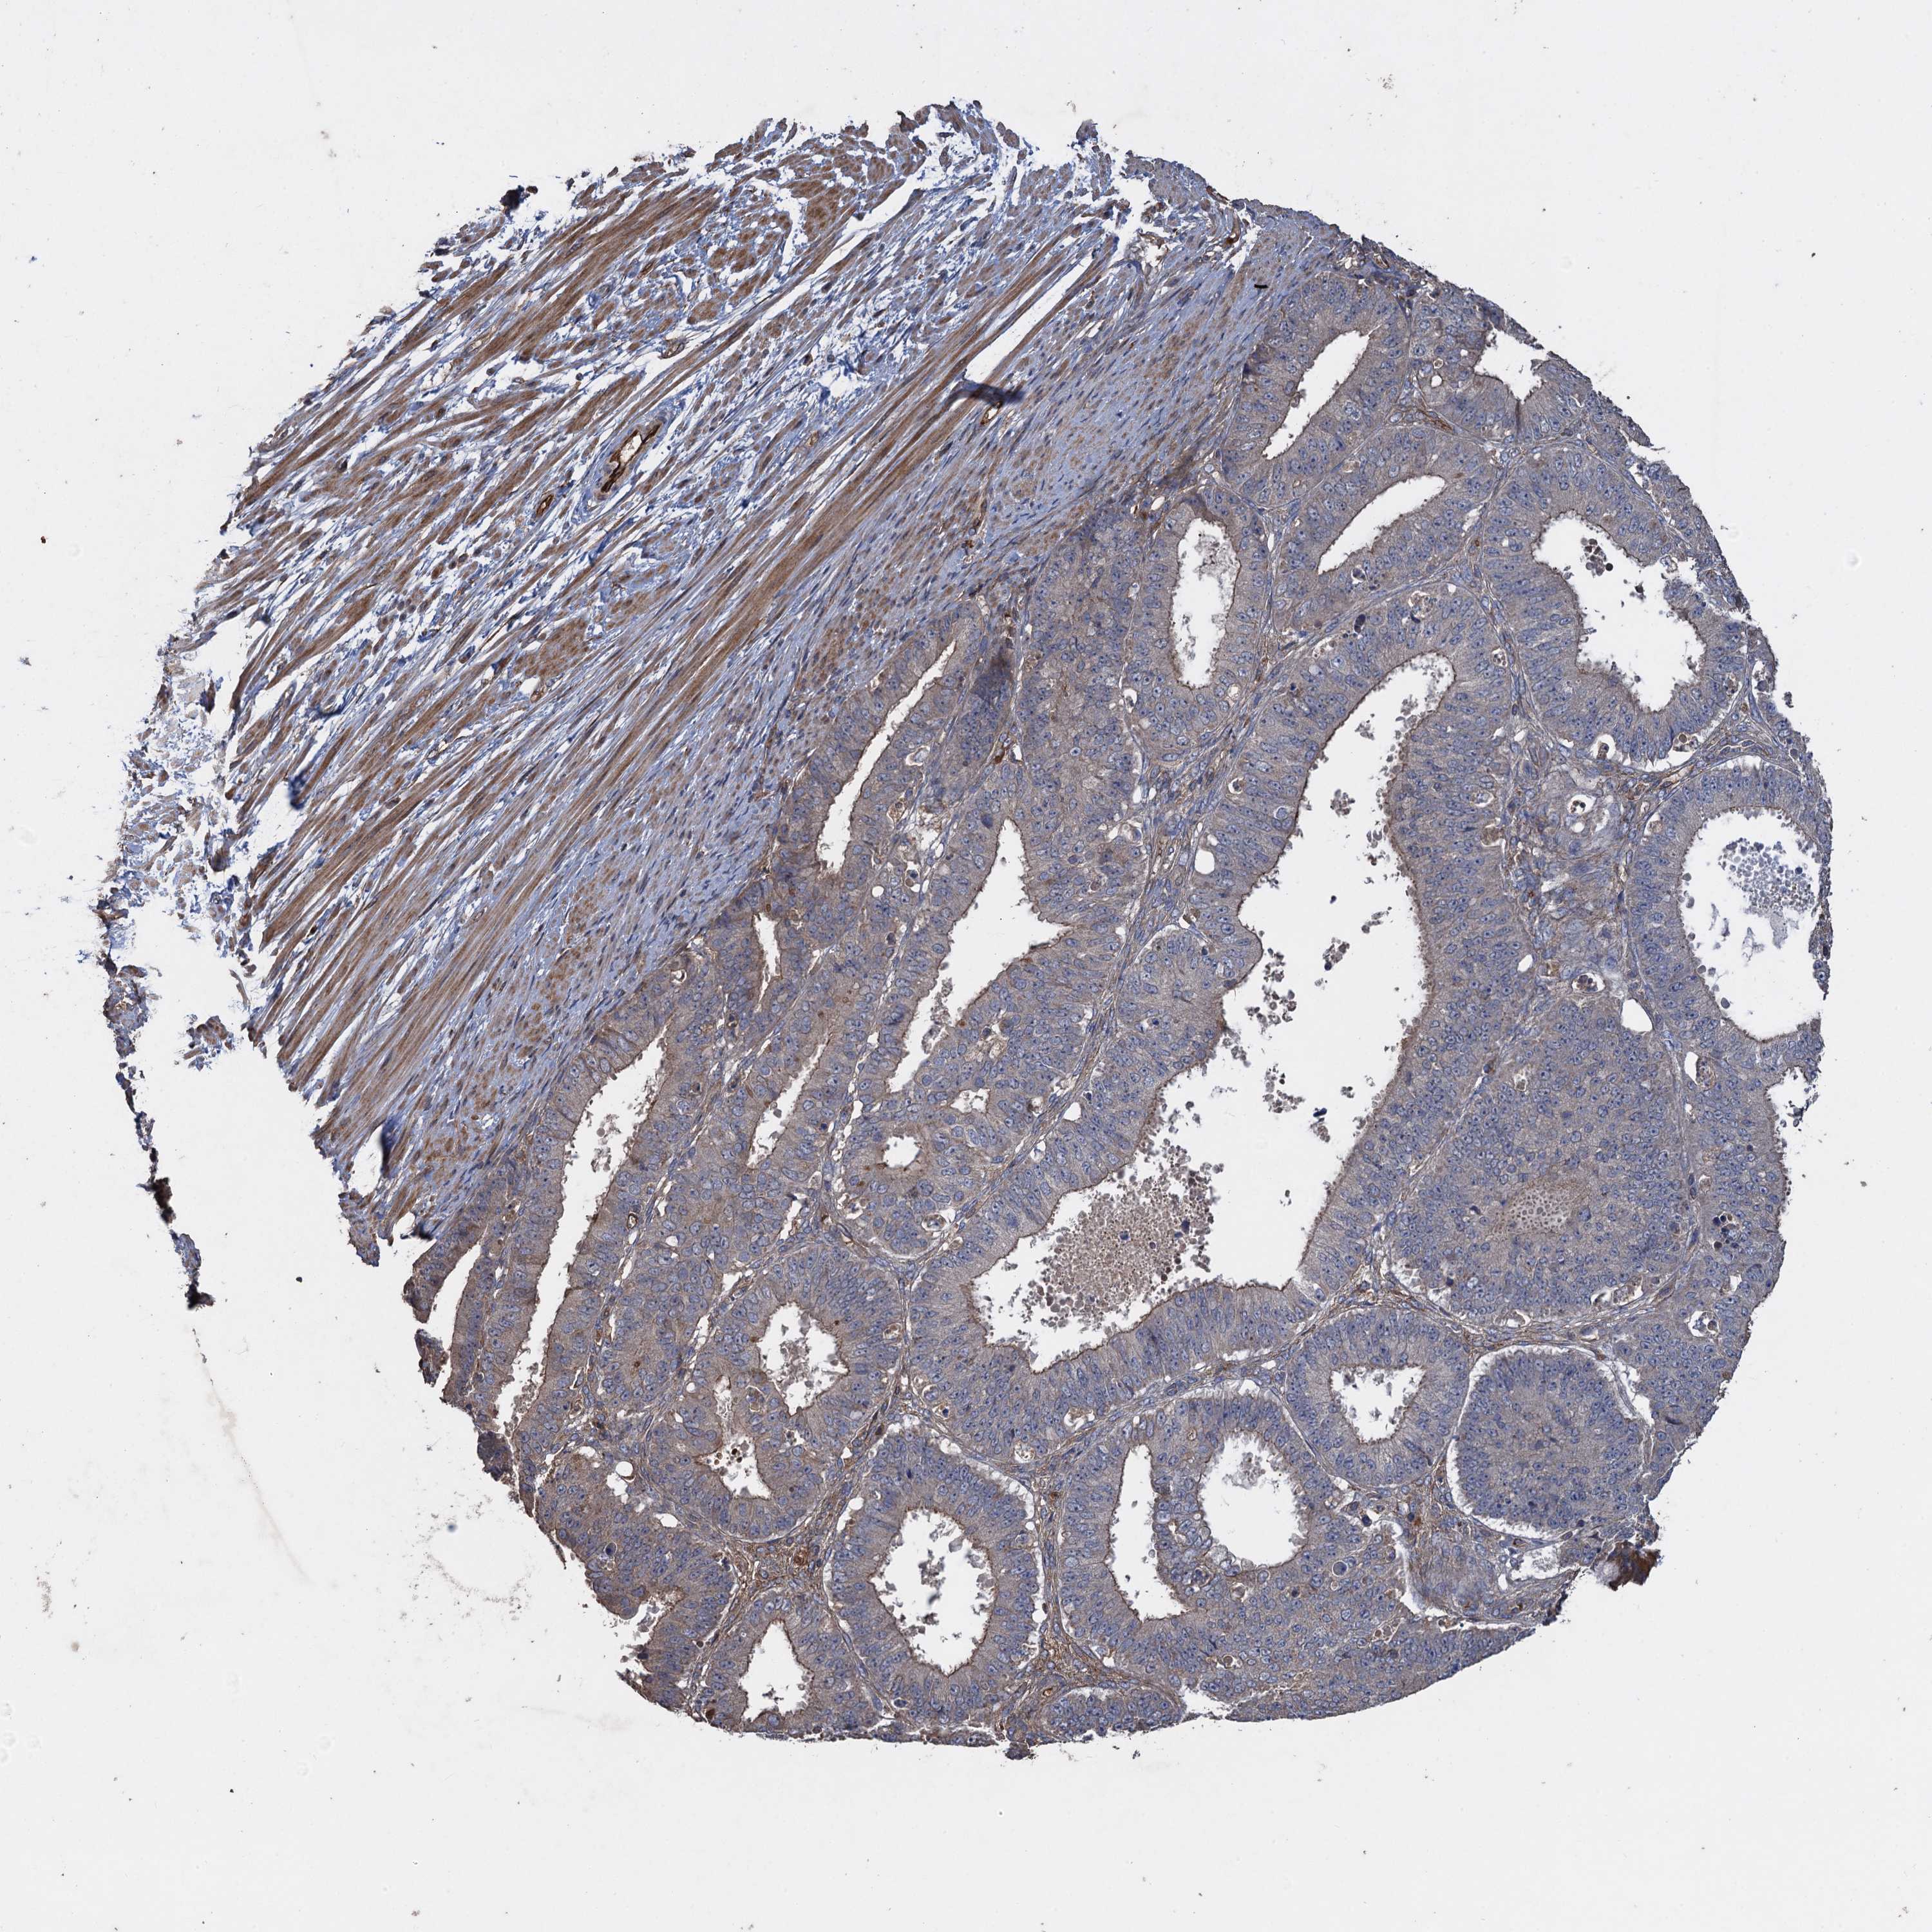

OVARIAN CANCER - Protein expressioni

A mouse-over function shows sample information and annotation data. Click on an image to view it in a full screen mode. Samples can be filtered based on level of antibody staining by selecting one or several of the following categories: high, medium, low and not detected. The assay and annotation is described here.

Note that samples used for immunohistochemistry by the Human Protein Atlas do not correspond to samples in the TCGA dataset.

Antibody stainingi

Antibody staining in the annotated cell types in the current human tissue is reported as not detected, low, medium, or high, based on conventional immunohistochemistry profiling in selected tissues. This score is based on the combination of the staining intensity and fraction of stained cells.

Each image is clickable and will lead to virtual microscopy that enables deeper exploration of all samples and also displays staining intensity scores, fraction scores and subcellular localization as well as patient and tissue information for each sample.

Antibody HPA041174

Antibody HPA041390

Cystadenocarcinoma, serous, NOS